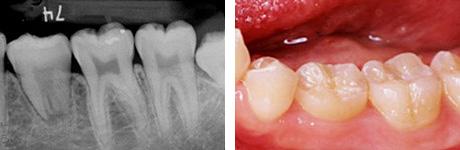

e、f : 移植後6ヶ月

g、h : 移植後3年